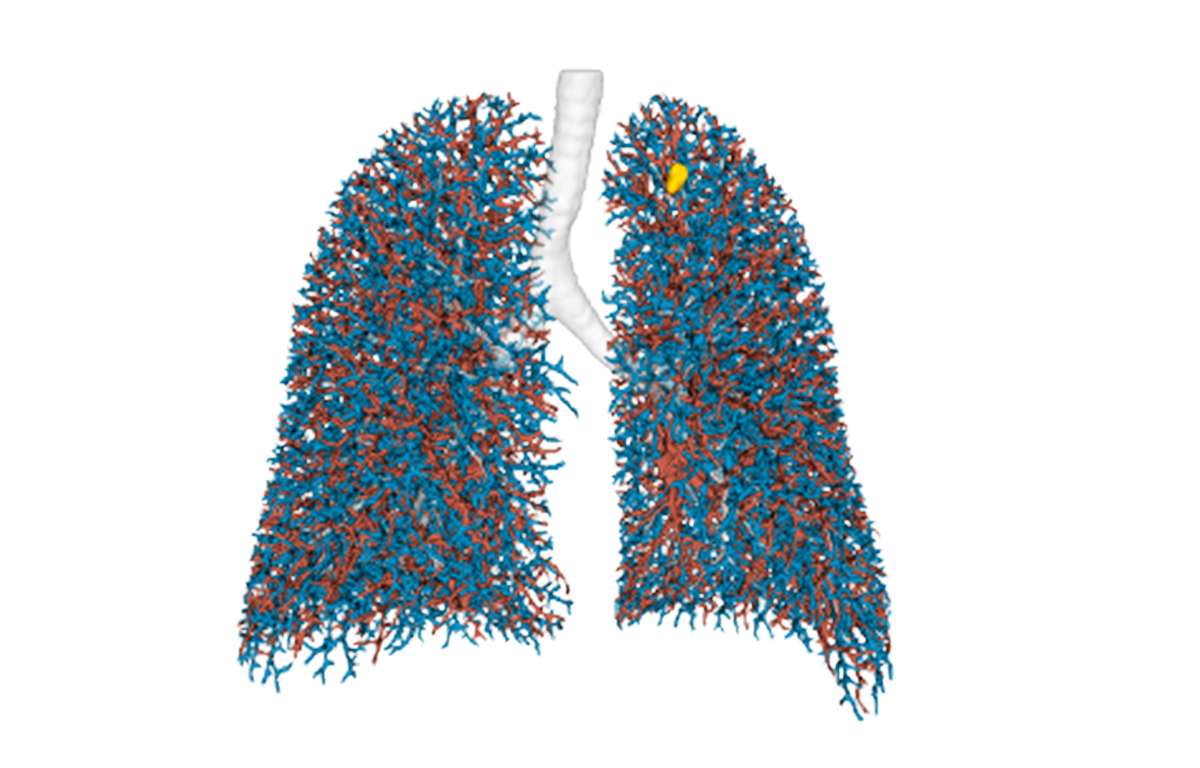

Built on advanced capabilities in lung segmentation and quantification, our AI technology interprets thoracic CT data with anatomical precision - capturing airway trees, parenchymal patterns, and vascular structures, even in severely diseased lungs.

- Segmentation of anatomical structures up to sub-segmental level

- Anatomical mapping to support navigation planning and guidance

Pre-operative planning of virtual bronchoscopy pathways

- Peripheral Lung Nodule Biopsy

- Tumor Ablation